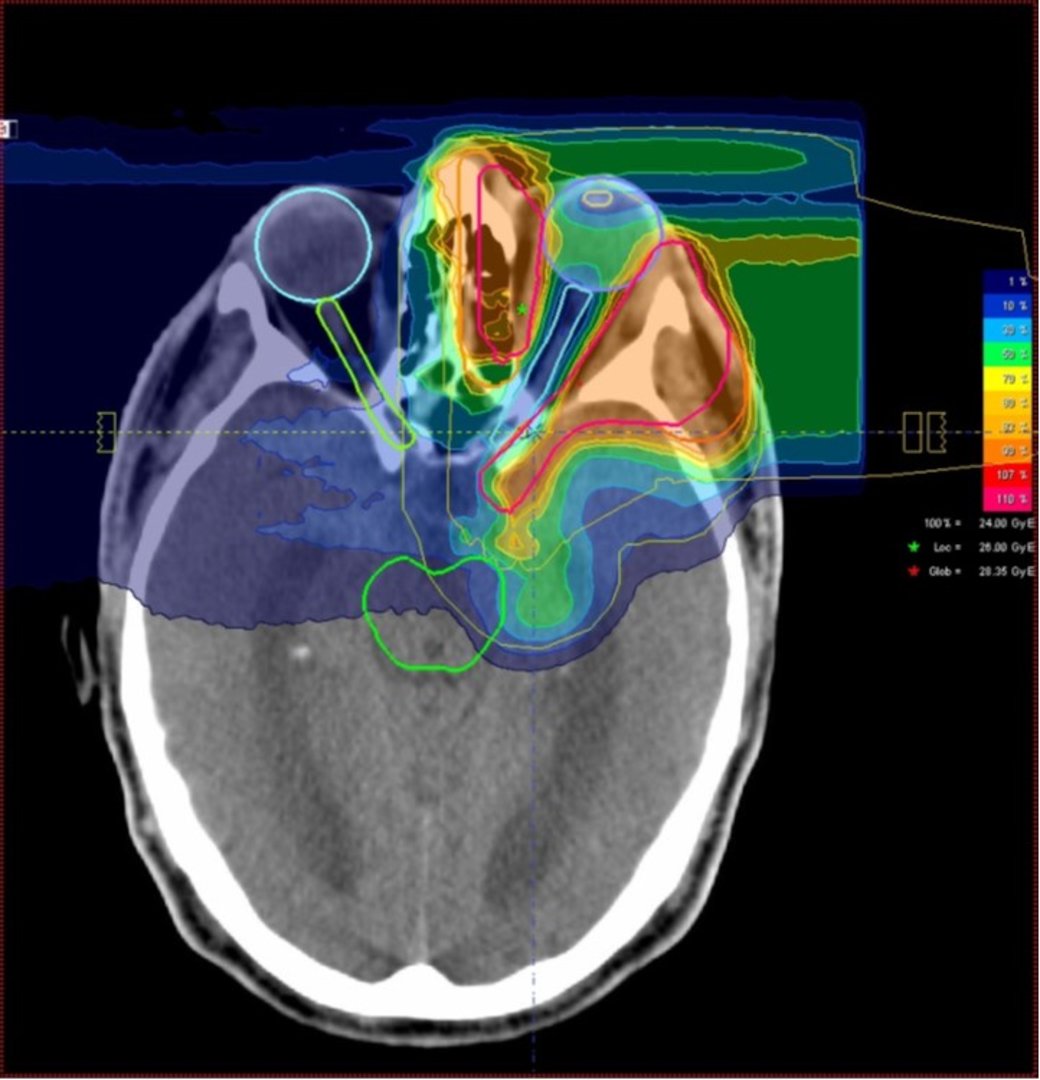

Ionenstrahlen eignen sich aufgrund ihrer besonderen physikalischen und biologischen Eigenschaften besonders für die hochpräzise Bestrahlung von Tumoren im Rahmen einer strahlentherapeutischen Behandlung von Krebspatienten.